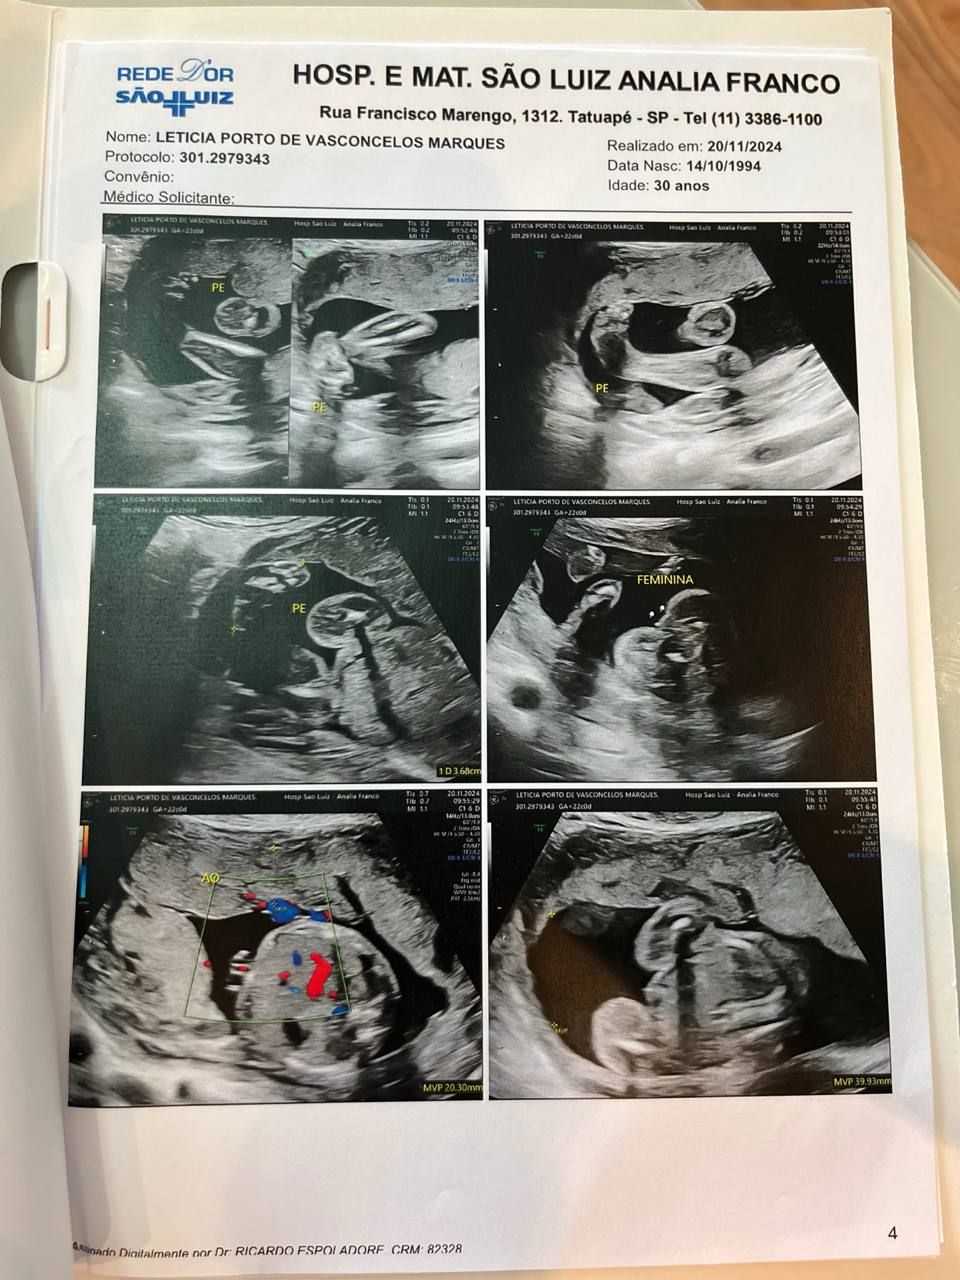

A alegria do livramento trouxe alívio, mas, semanas depois, após o segundo exame morfológico, algo corriqueiro na gravidez, outro desafio surgiu: Aurora tinha uma má-formação. “Pra gente foi uma surpresa muito grande, porque já tínhamos feito o primeiro exame morfológico, com 12 semanas, e estava tudo bem”. Para o casal era difícil entender como tudo estava bem e agora, com mais de 20 semanas, receber esse diagnóstico.

“Quando o médico pediu para conversar conosco novamente, na hora, já me bateu aquele gelo”, disse ela a respeito de como se sentiu após o exame. “Aos meus olhos, dava pra ver que um dos pés era pra dentro. Ele ainda não conseguia dizer se era só na perna, se eram os dois pés, mas identificou isso”, afirmou a mãe.

Mesmo diante do diagnóstico, o casal decidiu permanecer firme na Palavra. Letícia conta que optou por não compartilhar o diagnóstico com outras pessoas durante boa parte da gestação. “Eu tinha muita expectativa de fazer um ultrassom e ouvir que os pés estavam perfeitos. Mas, a cada exame, os médicos confirmavam a má-formação”, contou Letícia.

Até um dia antes do parto, os exames continuavam mostrando os dois pés tortos. Mesmo assim, o casal permaneceu crendo. No dia do nascimento, Letícia lembrou da primeira pergunta que fez ao marido. “Quando ela nasceu, eu perguntei: ‘Como ela está?’. Ele sabia que eu falava das pernas”, contou.

O diagnóstico anterior indicava “rotação medial bilateral dos pés” e sugeria “pé torto bilateral”. Outro médico também havia confirmado a suspeita. Porém, após o nascimento, um ortopedista avaliou a bebê e trouxe uma resposta surpreendente. “A primeira pergunta dele foi: ‘O que falaram para vocês sobre Aurora?’. Quando contamos o diagnóstico, ele respondeu: ‘Não sei por que disseram isso. Ela não tem nada. Ela é perfeita’”, contou Letícia.